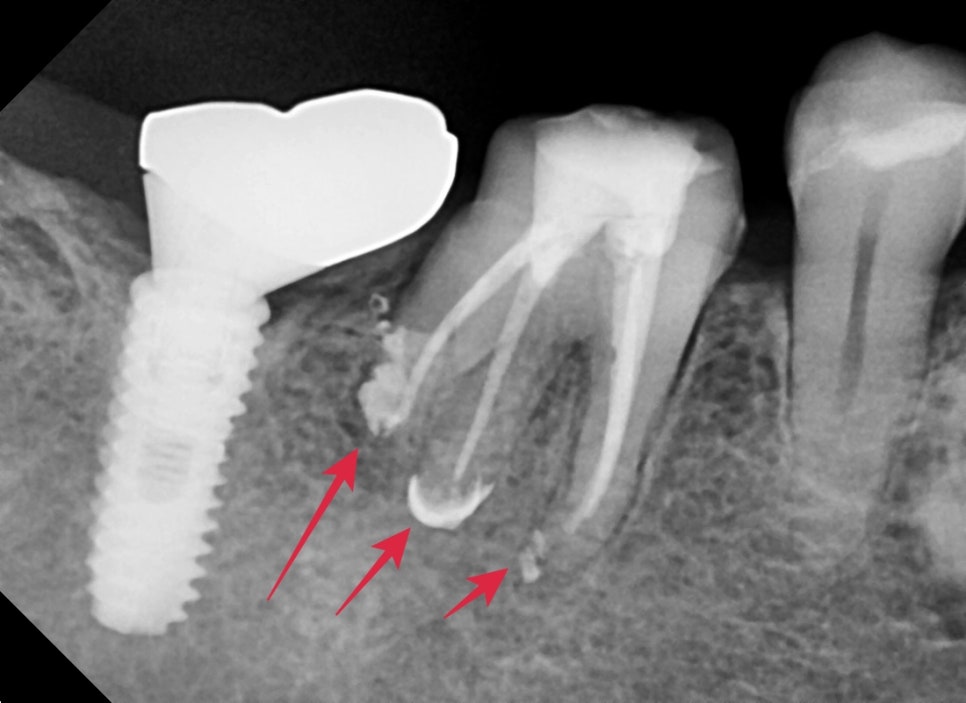

큰 엑스레이상에서 확인할 때 과거에 크라운치료를 받은 치아의 뿌리 주변이 염증소견이 보였습니다.

자세하게 확인하기 위해 해당 치아만 따로 엑스레이 촬영을 했습니다

어금니 뿌리가 4개가 있는데 모두 뿌리 쪽의 염증이 확인되었습니다.

통증이 있던 이유는 염증이 생기면서 압력이 생겨 불편감을 호소하시는 중이었습니다.

신경치료가 끝난 직후의 엑스레이 사진입니다.

염증이 심했던 치아는 뿌리끝 쪽이 신경관을 밀봉하는 재료가

화살표와 같이 뿌리끝까지 밀려나오며 바깥쪽까지 밀봉해 주는 경우가 있습니다.

물론 해당 재료는 생체친화적이기 때문에 추후 일부는 흡수가 되기도 합니다.